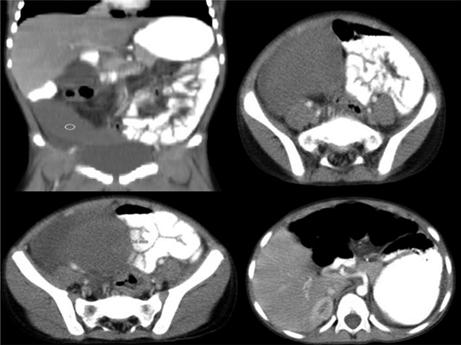

Al ingreso, se encontró con deshidratación grado I, con taquicardia, febril y sensación de masa a nivel de fosa ilíaca derecha, dolorosa a la palpación y sin signos de irritación peritoneal. Se consideró inicialmente que cursaba con probable plastrón apendicular, por lo que se inició manejo antibiótico (ampicilina/ sulbactam), líquidos endovenosos y reposo intestinal. Los paraclínicos de ingreso mostraron leucocitosis 21.400 cel/mm3 con neutrofilia y proteína C reactiva negativa. Se realizó TACc con hallazgo sugestivo de bazo ectópico, torsión del pedículo vascular y compromiso isquémico (Ver Figura 2), razón por la cual se decidió llevar a laparoscopia exploratoria de urgencia.

Figura 2 TACc abdominal: bazo ectópico a nivel de fosa ilíaca derecha con líquido periesplénico

A pesar del antecedente de FN en nuestro paciente, la impresión diagnóstica inicial fue plastrón apendicular, razón por la que se solicitó TACc (Ver Figura 2), en el que se logró el diagnóstico de bazo ectópico con torsión del pedículo y se llevó a cirugía de urgencia.